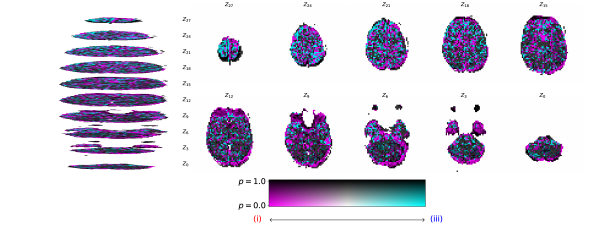

Converging to retrieve near scalp haemodynamical activity. One interesting phenomena that was observed by propagating relevances from the latent representations of the fMRI instance, , to the input, , was that the relevances in sub-cortical areas were neither positive nor negative, yielding residual relevance, as seen in Figure 6. This later observation suggests that haemodynamical activity from these areas does not significantly aids the targeted synthesis. Recall that the regularization term, , is used with the latent EEG and fMRI representations. This is in accordance with the fact that the retrievable information is in its majority next to the scalp, where the electrodes are placed. de Beeck and Nakatani [15] discuss how high frequencies are not able to travel significant distances with obstacles, such as white matter and the scalp, in between. We also report negative relevances on the visual cortex and positive relevances on the occipital and prefrontal lobes. Please note that negative and positive relevances represent relevant features, whereas when one has zero relevance, it means a feature was not relevant for the task. Daly et al. [8] found that neuronal activity retrieved from EEG can reflect the haemodynamical changes in subcortical areas. Here we claim that haemodynamical activity information in areas next to the scalp are relevant to learn the shared latent space.